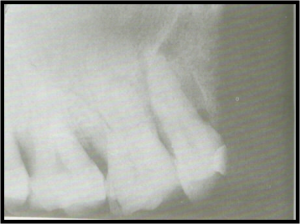

PROBLEM: PHALANGIOMA

CAUSE: Pt’s finger incorrectly placed in front of film instead of

behind the film. Pt’s finger appears on film.

ACTION: Avoid a phalangioma, make certain that the pt’s finger used to

stabilize the film is placed behind the film and not in front